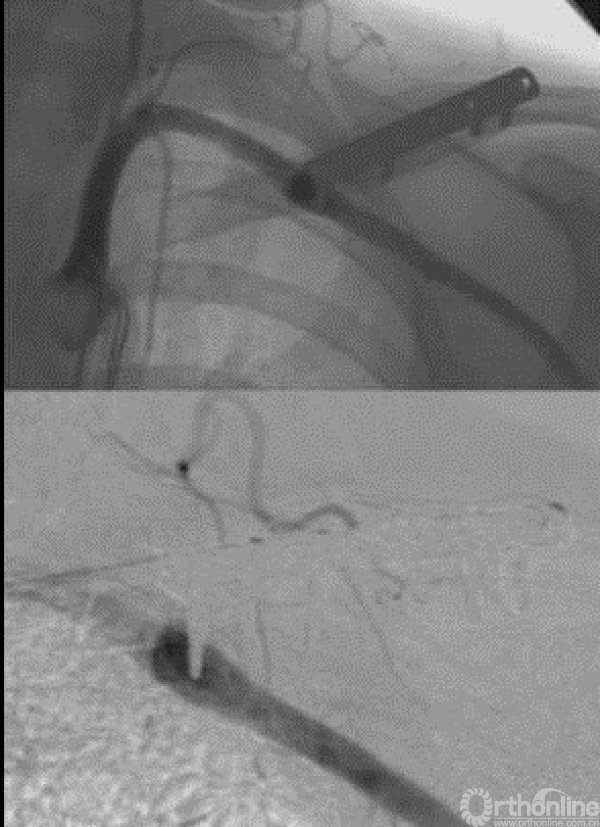

曾经有一例病例报道,进行了假性动脉瘤的切除。我们可以很清楚的看到这个血管和长的螺钉以及整个锁骨和钢板。

同时还有一些血管造影的证据也表明了该并发症。